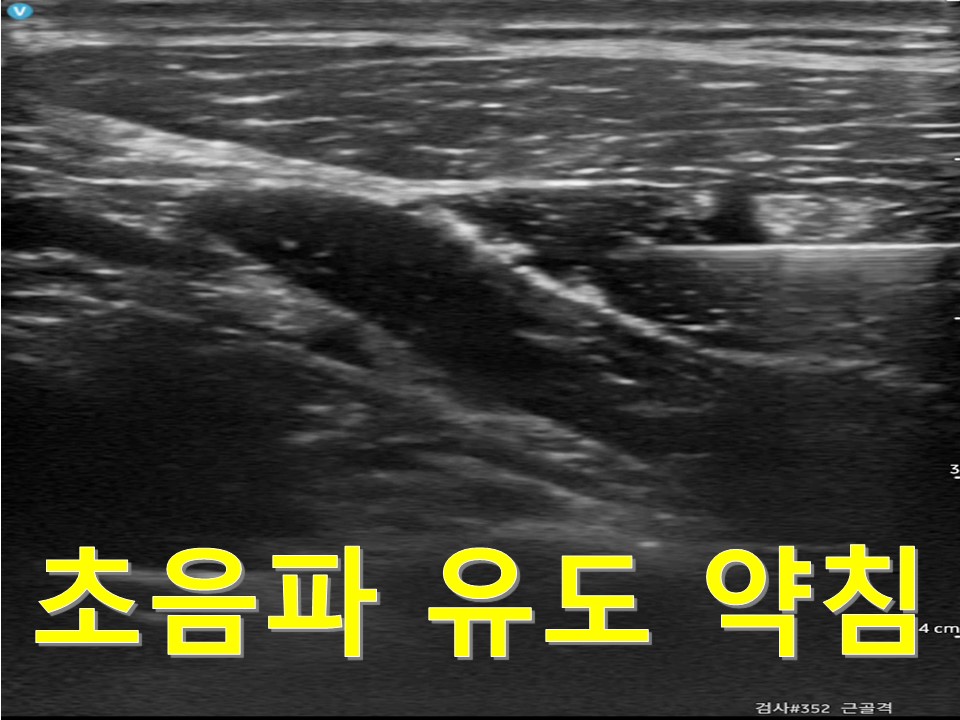

해당 치료는 한의사의 정확한 촉진 또는 초음파 유도 하에

정밀하게 시행되어 안전성과 효과를 높입니다.

초음파 유도 약침을 통해 유착 부위를 정확히 해소하고,

- 초음파 유도 약침: 신경 주변의 염증과 유착을 정밀하게 해소하여 신경 기능 회복에 중점을 둡니다.